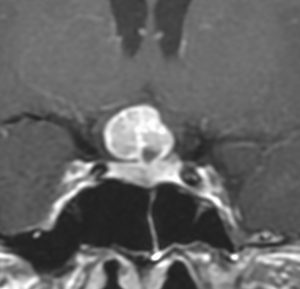

40代の女性に,軽度の両耳側半盲で発生したものです。視交叉と視床下部の下面に腫瘍があり,下垂体柄の位置が全くわからず,下垂体の前葉と後葉は侵されていません。ですから,下垂体柄から発生した腫瘍であり,pituicytomaが強く疑われます。T2ではほぼ等信号,小さなのう胞があり,ガドリニウムで強く増強されます。手術では正常下垂体柄の一部が右側にうすく残っており,幸運にも亜全摘出できて下垂体機能は温存できました。残存腫瘍は増大傾向を示していません。でも,このようなタイプを積極的に摘出すると,汎下垂体機能低下症を招くことが多いので,手術するかどうかの判断はとても難しいです。